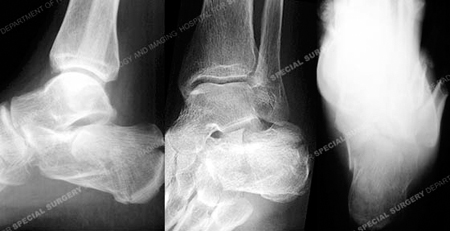

An injury radiographs revealing a calcaneus fracture.

A 68-year-old male was involved in a motor vehicle accident when the car he was driving was struck from behind and pushed into the vehicle in front of him. He was brought to the HSS Orthopedic Trauma Service with complaints of left foot pain and radiographs revealed a left-sided, displaced, intra-articular calcaneus (heel bone) fracture with a depressed articular segment. Fracture surgery was performed by Dr. David L. Helfet using a minimally invasive technique with elevation of the depressed segment, reduction and fixation of the posterior facet and tuberosity including interfragmentary lag screws. He returned at regular follow-up intervals and healed uneventfully, and at 6 months following surgery he presented with good radiographic and clinical results including a healed calcaneus fracture, significant improvement of pain symptoms, and a return to his prior activities of daily living.